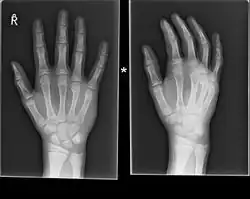

Boxer fracture

Boxer fracture of the 4th and 5th knuckles